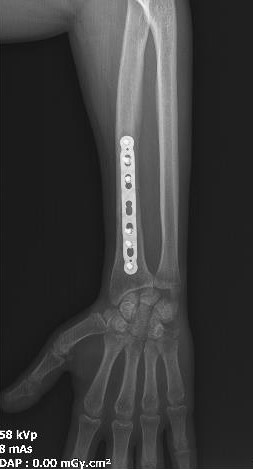

TRUE LOCK 3.5mm Ulna Radius Plate

TRUE LOCK 3.5mm Ulna Radius Plates are indicated for fractures of ulna, radius and fibula shaft.

Images Gallery